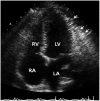

Pneumopericardium is a rare complication of pericardiocentesis, occurring either as a result of direct pleuro-pericardial communication or a leaky drainage system. Air-fluid level surrounding the heart shadow within the pericardium on a chest X-ray is an early observation at diagnosis. This clinical measurement and process is variable, depending on the hemodynamic status of the patient. The development of a cardiac tamponade is a serious complication, necessitating prompt recognition and treatment. We recently observed a case of pneumopericardium after a therapeutic pericardiocentesis in a 20-year-old man with tuberculous pericardial effusion.